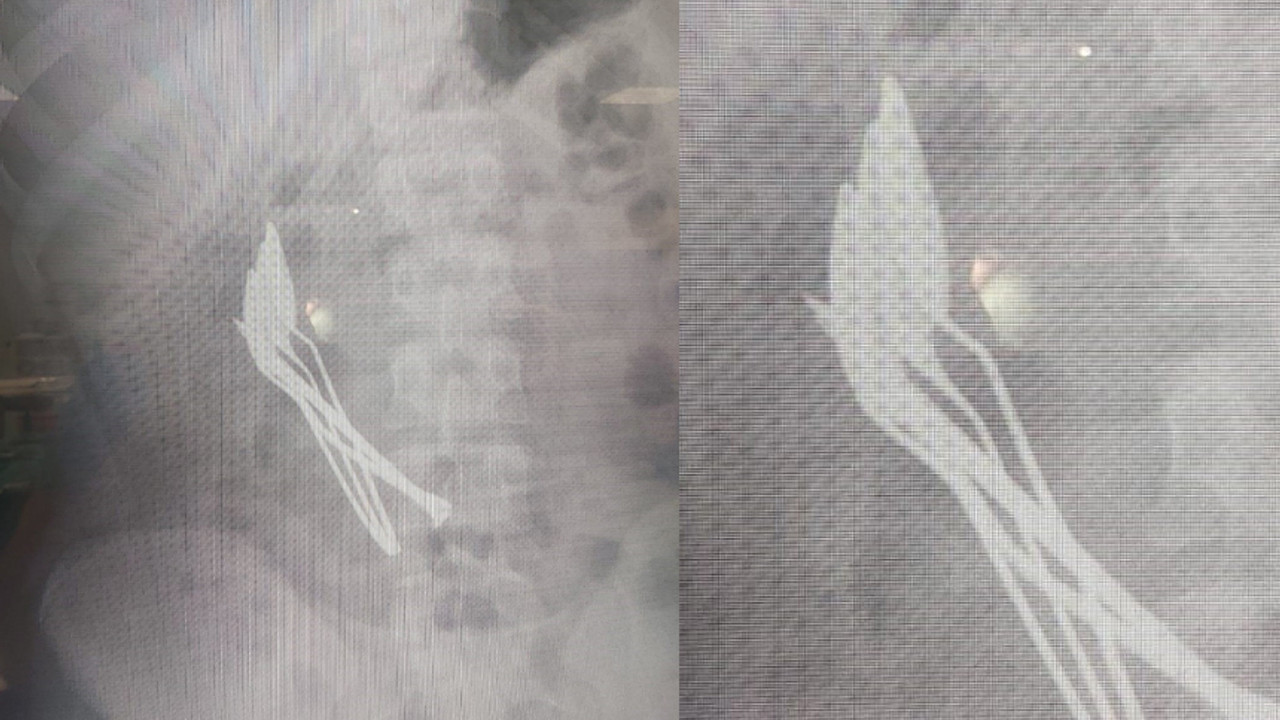

Kayseri'de yaşayan 15 yaşındaki çocuk, mide ağrısı şikayetiyle Kayseri Şehir Hastanesine başvurdu. Yapılan ilk müdahalede çocuğun röntgeni çekilirken, midesinde cisim fark edildi.

Çocuk Cerrahisi ve Ürolojisi Anabilim Dalı Başkanı Doç. Dr. Mustafa Erman Dörterler tarafından ameliyata alınan çocuğun midesinden 4 adet metal çay kaşığı ve çivi çıkarıldı. Bir süre tedavisine hastanede devam edilen çocuk, taburcu edildi.